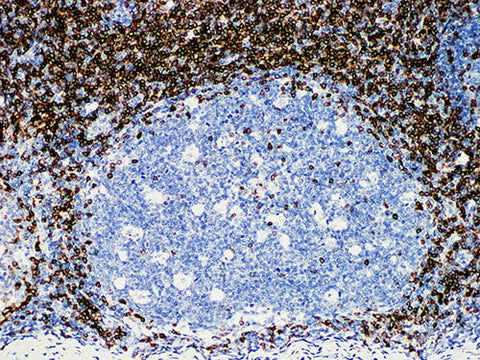

CD5 Monoclonal Antibody Stored at -20°C

Applications IHC-P

Tissue Specificity Tonsil

CD5 antigen is a transmembrane glycoprotein, which is expressed on the surface of almost all mature human T cells (about 10% of CD4 + T cells are CD5 -). In immature (CD34 +) T cells, the expression of CD5 is weak, and the expression intensity increases with maturation. CD5 is also expressed in a small number of normal human B cells (20% of B cells were in peripheral blood, scattered in the mantle region of lymph nodes).